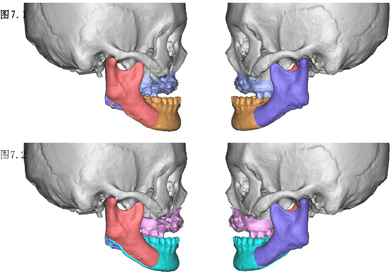

上颌骨植骨术后半年,伤口愈合良好。完善影像学检查和头影测量分析,按照治疗方案进行Ⅱ期正颌手术纠正骨性反he(牙合)。数字化虚拟方案如下,上颌骨Le Fort I型截骨前徙3mm,下颌骨矢状劈开术后退2mm(图7)。